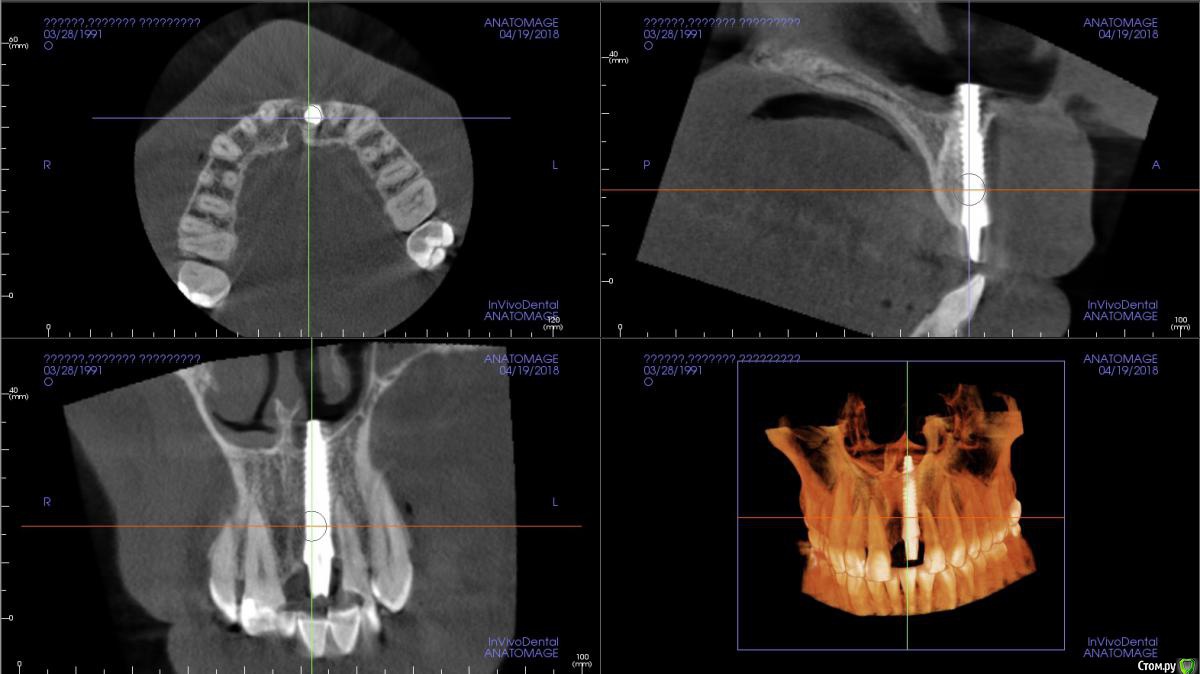

Irouil Опубликовано 23 августа, 2018 Автор Поделиться Опубликовано 23 августа, 2018 Дабы не плодить темы, ситуация близкая по форме, но иная по содержанию. Снаружи - вестибулярно зенит смещен миллиметра на 2-3, слизистая на имплантате, очеееень тонкая, горизонтально визуальный провал.Но есть и позитив. Сосочки на месте. Я хотел пока ограничиться мягкими тканями. Нааугментировать в два этажа, вестибулярно вдоль имплантата с неба, пришеечно с бугра, оставить на три месяца. Дальше смотреть по настроению пациента. Вариант с удалением пока не рассматриваем, пациент радикально против Ссылка на комментарий

колесников Опубликовано 23 августа, 2018 Поделиться Опубликовано 23 августа, 2018 ОМГ! 1 Ссылка на комментарий

Irouil Опубликовано 23 августа, 2018 Автор Поделиться Опубликовано 23 августа, 2018 ОМГ!Кто-то очень искал торка) хорошо, до лба не дотянулись 1 Ссылка на комментарий

Dman Опубликовано 24 августа, 2018 Поделиться Опубликовано 24 августа, 2018 какая длина импланта? 18-20? Ссылка на комментарий

Irouil Опубликовано 24 августа, 2018 Автор Поделиться Опубликовано 24 августа, 2018 какая длина импланта? 18-20?20, да. Диаметр в шейке 4.2-4.5 Ссылка на комментарий

Dman Опубликовано 24 августа, 2018 Поделиться Опубликовано 24 августа, 2018 а что за система? Ссылка на комментарий

kamranchick Опубликовано 24 августа, 2018 Поделиться Опубликовано 24 августа, 2018 Дабы не плодить темы, ситуация близкая по форме, но иная по содержанию. Снаружи - вестибулярно зенит смещен миллиметра на 2-3, слизистая на имплантате, очеееень тонкая, горизонтально визуальный провал.Но есть и позитив. Сосочки на месте. Я хотел пока ограничиться мягкими тканями. Нааугментировать в два этажа, вестибулярно вдоль имплантата с неба, пришеечно с бугра, оставить на три месяца. Дальше смотреть по настроению пациента. Вариант с удалением пока не рассматриваем, пациент радикально противкак вариант сформировать такой разрез, сошлифовать все витки имплантата с вестибулярной стороны, для создания места для десенки, и пришить дсдт с неба либо с бугра, альтернатив не вижу на данный момент Ссылка на комментарий